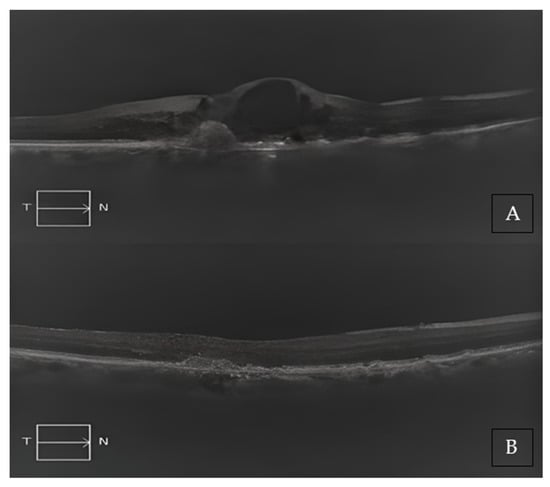

Two representative cases of patients from our cohort, before and after treatment with Brolucizumab, are shown in Figure 2A,B and Figure 3A,B.

Figure 3. (A) Baseline SD-OCT scan acquired with Maestro 3D OCT-1 (Topcon Corporation, Tokyo, Japan) of a treatment-naïve patient displaying a large, pigmented epithelium detachment (PED), and subretinal edema. (B) A 4-month SD-OCT scan acquired with Maestro 3D OCT-1 (Topcon Corporation, Tokyo, Japan) displayed a complete reabsorption of the PED and a modest residual sub-RPE hyper-reflective band.